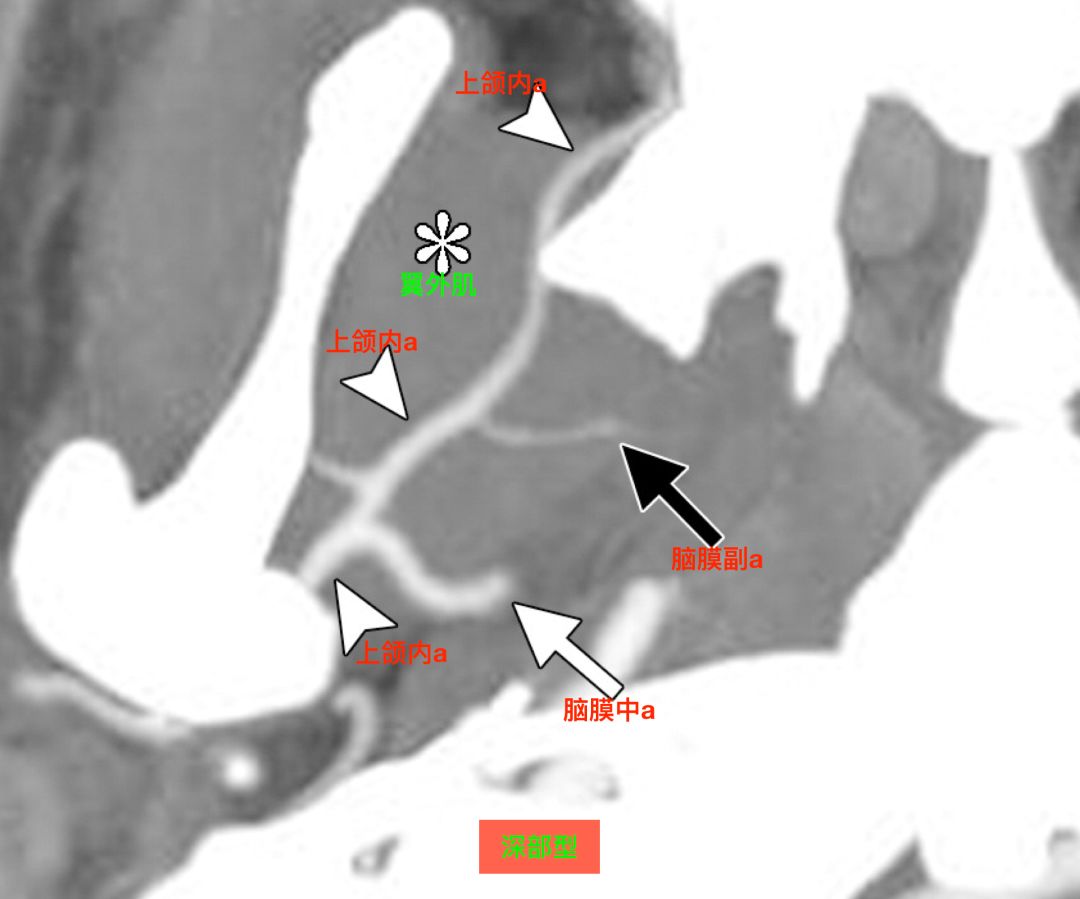

在CTA上,也可以区分浅部型和深部型。

CTA,深部型,上颌内动脉走行于翼外肌深面,脑膜中动脉和脑膜副动脉分别发自上颌内动脉(Tanoue 2013)。

![]()